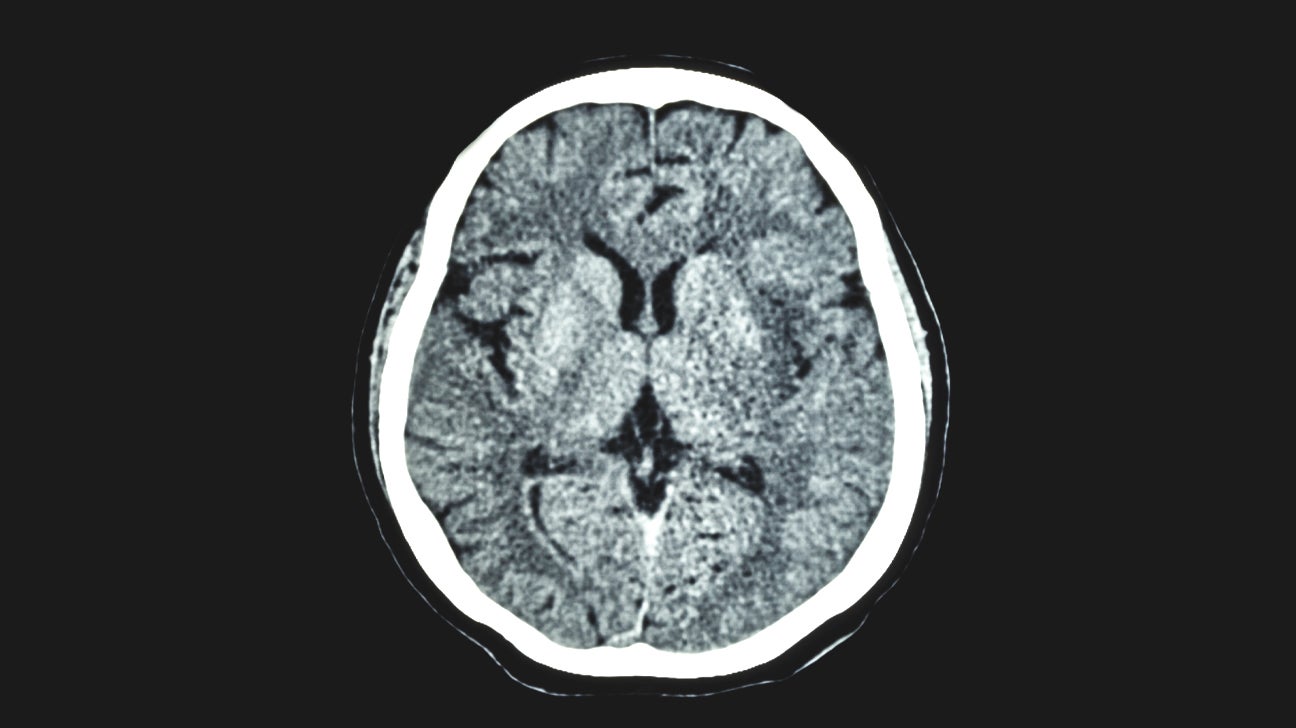

Computed Tomography (CT Or CAT) Scan Of The Brain | Johns Hopkins Medicine

www.hopkinsmedicine.org

www.hopkinsmedicine.org

Brain Ct Scan Report Sample Pdf - Barebonestory

barebonestory.blogspot.com

barebonestory.blogspot.com